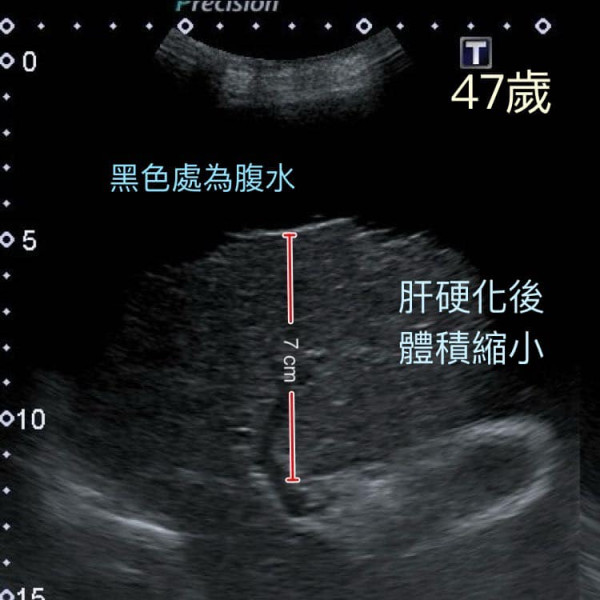

錢醫生將病患當年的舊片與最新的斷層掃描及超聲波影像比對,驚覺其肝臟邊長減少了30%,推算體積只剩下原來的1/3,肝臟萎縮情況相當嚴重。由於肝臟硬化縮小,導致肝門靜脈壓力上升,血液無法回流,持續產生大量腹水。此時,唯一的治療方法只剩下換肝